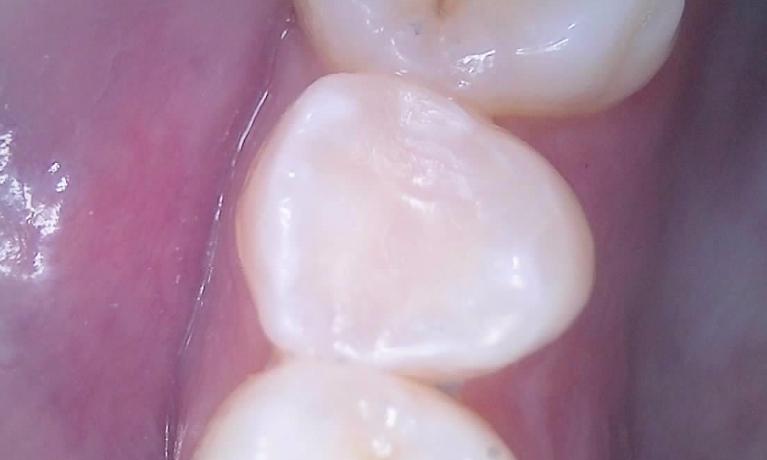

We take great pride in the services we perform in our office. We always try to not only meet your expectations, but we also try to exceed them. There are many types of services that we perform in our office, as well as others that we perform in coordination with highly skilled specialists. We have compiled a few examples of the treatments that we have performed. We are proud to say that these are the usual results our patients expect to see.

The photos are not retouched, nor are they taken by a professional photographer. These are just the routine treatment photos that we take and the results that we see every day. They are by no means a comprehensive catalog of the procedures that we perform. They are just a small sample of some of the results you can expect when you seek treatment in our office.